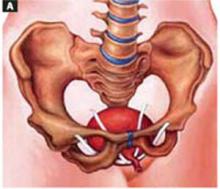

FIGURE 10 Routes of transobturator and retropubic slings

Graphic depiction of both the transobturator sling and the retropubic tension-free sling in place.

Fluoroscopic image of both slings in a cadaver. The transobturator sling runs horizontally while the retropubic tension-free sling forms a tighter “U.”